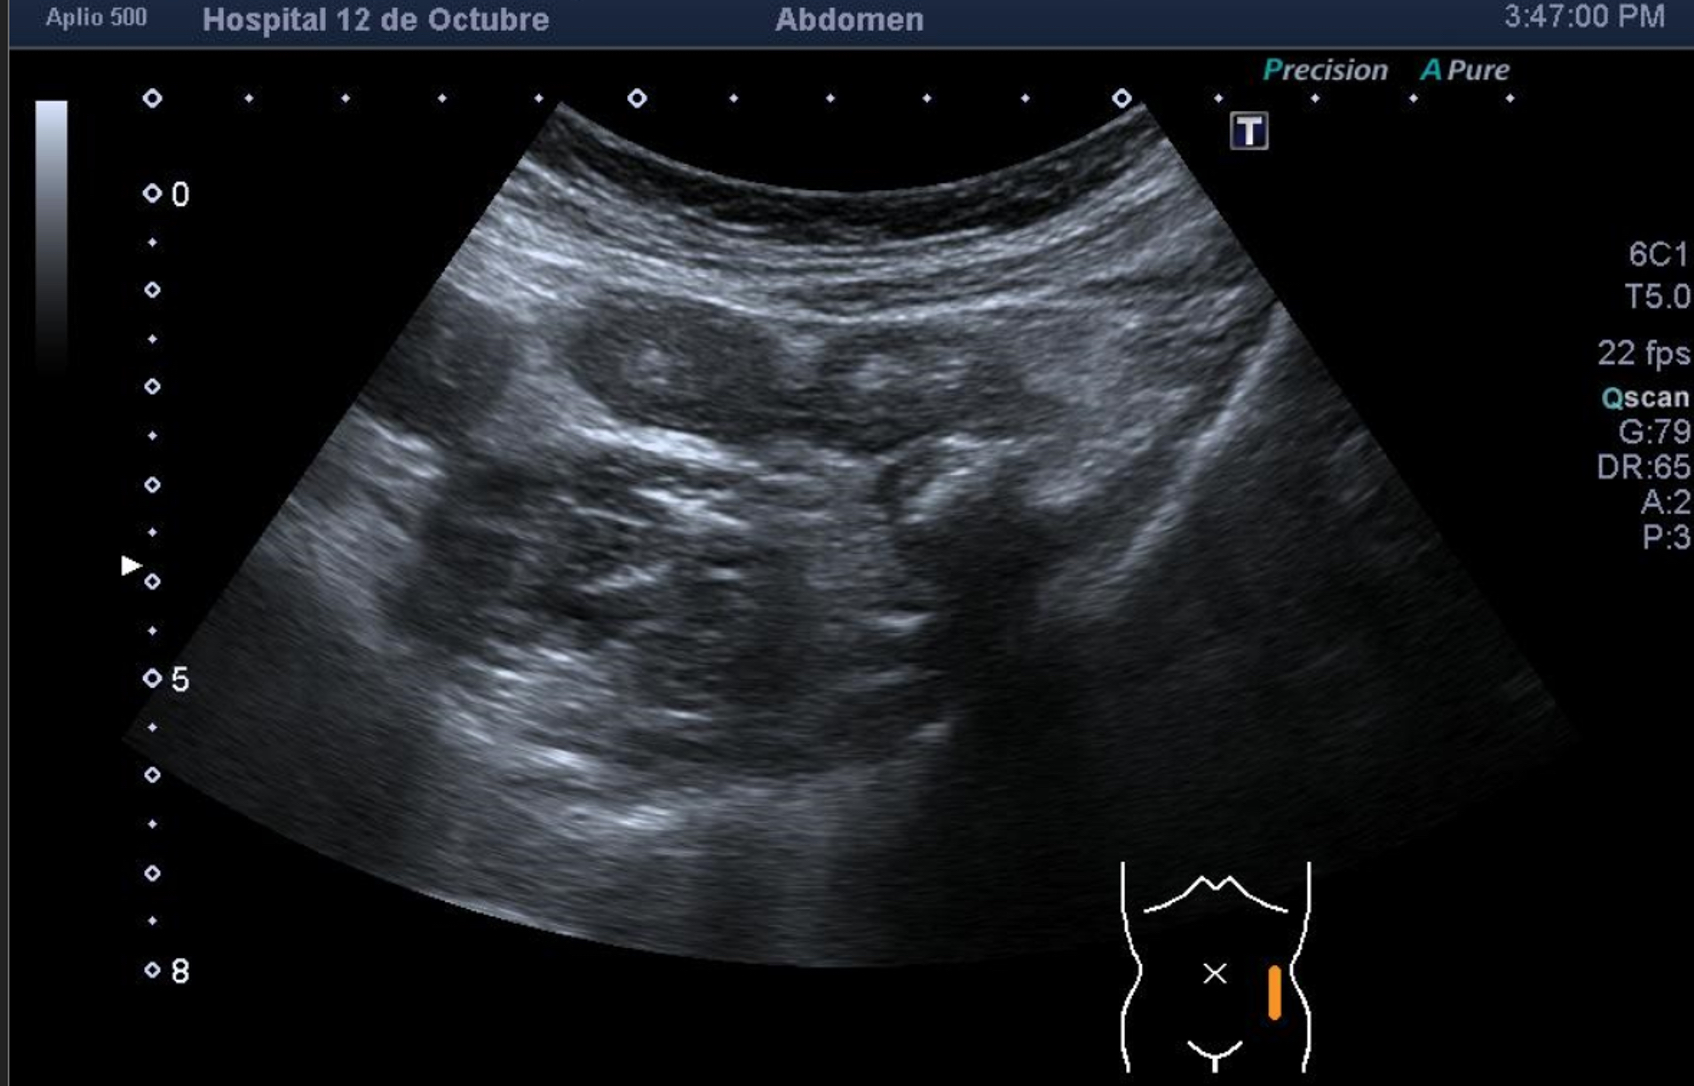

Se explora FII-hipogastrio y en el punto de más dolor se observa engrosamiento de asas de intestino grueso sin peristaltismo y con signos de edema de la grasa adyacente. No líquido libre.

También se realiza ecografia en urgencias del hospital.

En el hospital se realiza una nueva ecografía en el servicio de radiología confirmando el diagnóstico de sospecha: diverticulitis aguda en sigma distal sin datos de complicación. Hinchey 1A.